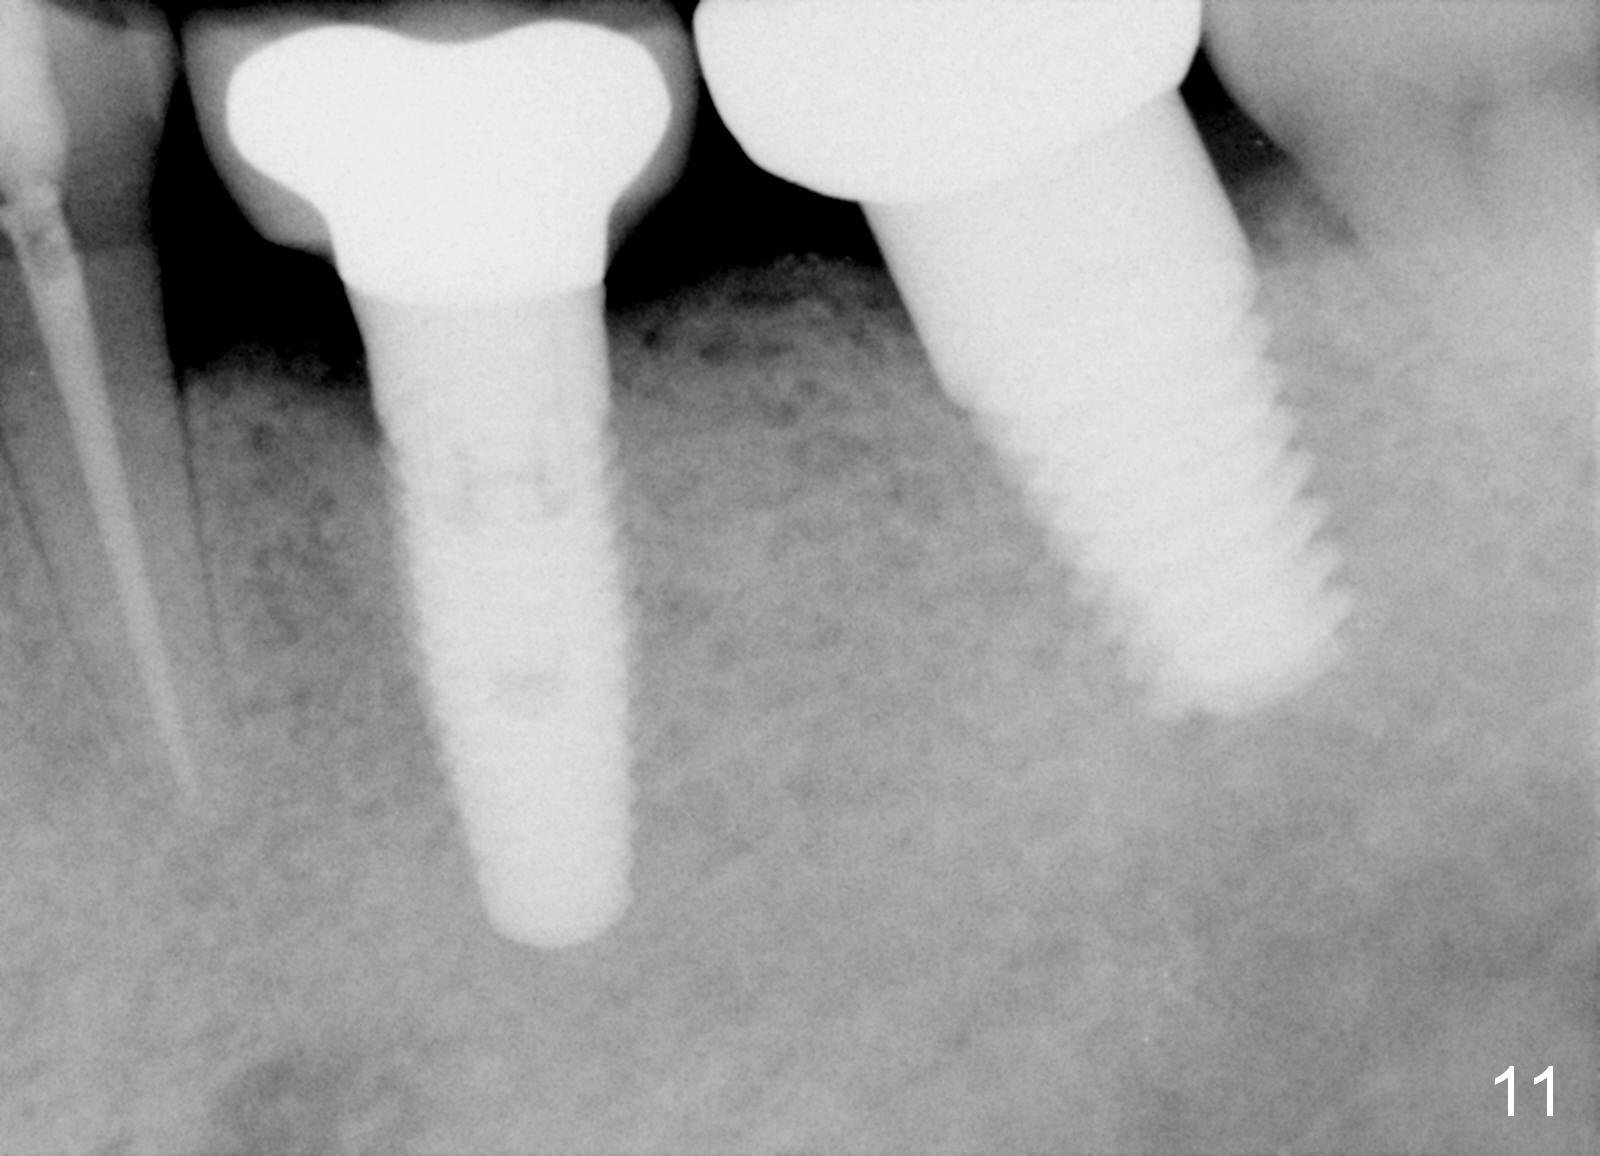

A 63-year-old man has lost a crown from the tooth #18 (Fig.1), which is tender to percussion. The margin is subgingival.

CBCT reveals periapical radiolucency (Fig.2 ^). The tooth appears to be nonsalvageable. The root is 11 mm long. There is 5 mm bone between the fused apex and the inferior alveolar nerve. The prospective implant is going to engage 3 mm out of the 5 mm native bone for primary stability.